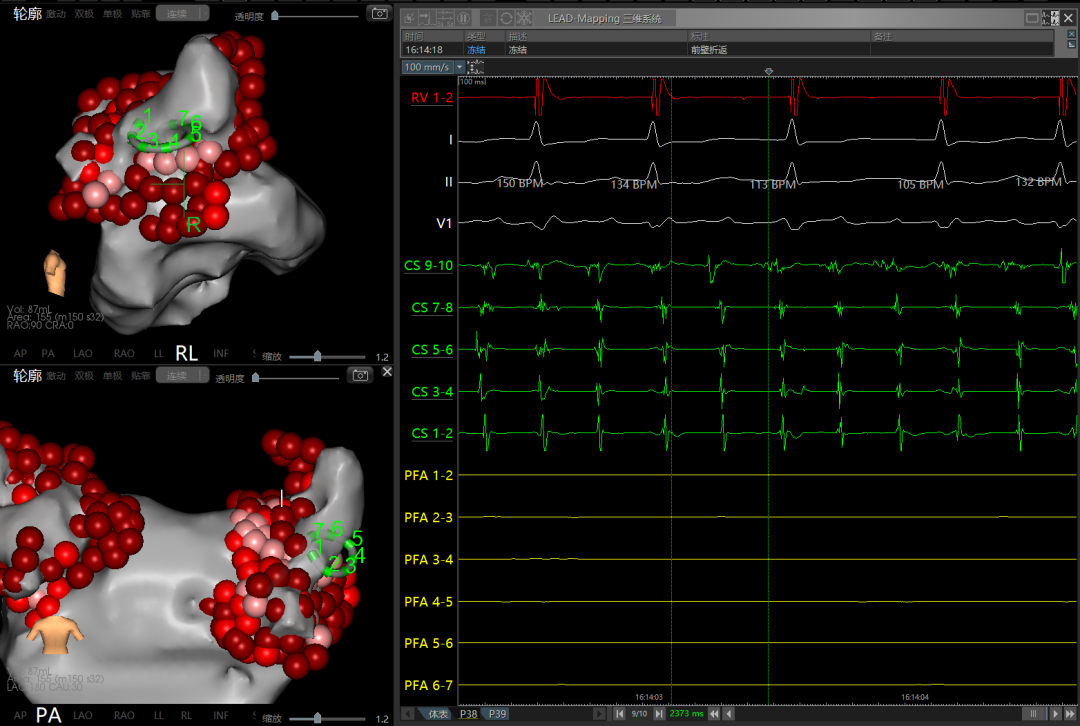

使用环形导管建模标测,患者后壁基质较好,前壁基质存在低电压区,左上肺静脉肌袖较深。

术中左侧和右侧肺静脉电位

左侧肺静脉消融触发房扑,先从左侧肺静脉开始消融,消融时触发短阵房扑,形态不断变化。优先隔离肺静脉,做完PVI后再观察房扑是否存在。

消融后左/右侧肺静脉电位

PVI后房扑:肺静脉隔离后,房扑仍在发作且持续稳定,CS90早,周长220-230ms,遂进行激动标测。